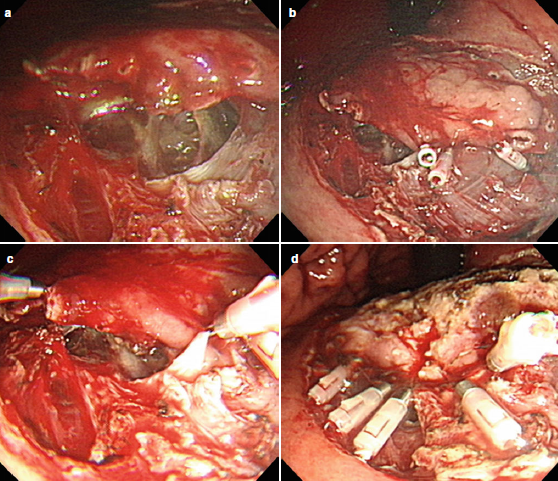

- Para la perforación durante la resección submucosa y mucosal en el tracto gastrointestinal los endoclips son la terapia de elección. Si el orificio es muy grande la aplicación de clips en los extremos puede reducir el diámetro y hacer más factible la aproximación de los bordes. Si esto falla un endoclip con endoloop puede ser efectivo.

- Existen 2 tipos de Clips: los que se colocan a través del endoscopio y los que se colocan sobre el endoscopio (OTSC). Los clips convencionales se utilizan en perforaciones pequeñas (menores a 1 centímetro). Los OTSC son efectivos en defectos menores de 2 centímetros.

- Se consideran superiores a los CLIPS convencionales porque abarcan más tejido, cierran defectos mas grandes y tienen más fuerza que los CLIPS.

- Limitaciones: requieren que el endoscopio sea extraído del paciente para montar el dispositivo.

- Sus mejores resultados se obtienen en los defectos menores a 2 centímetros.